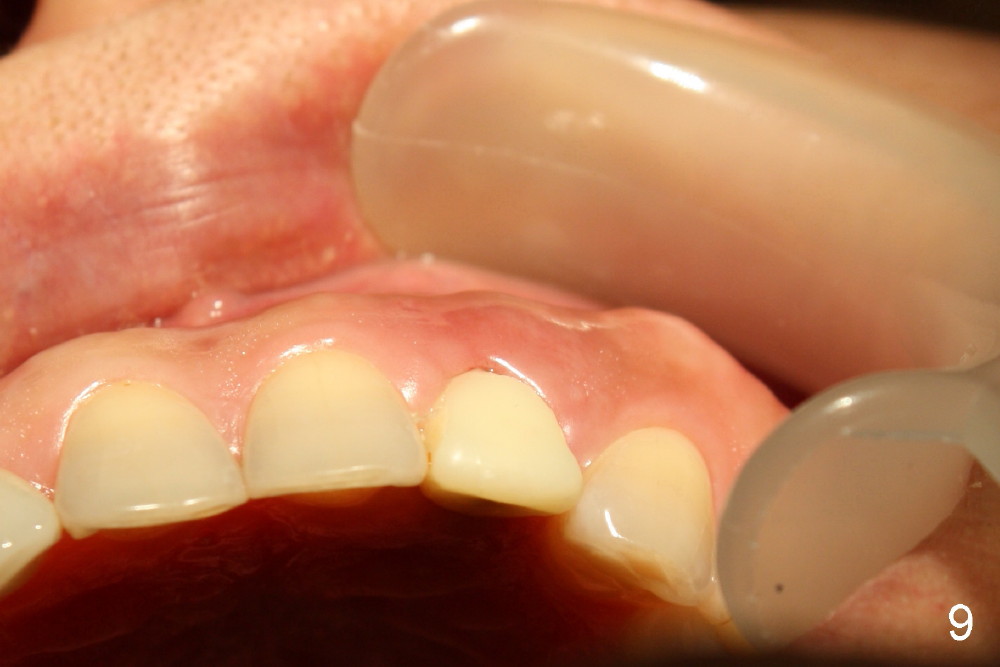

Within one week, the infection resolves (Fig.8,9).